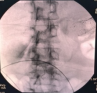

X线显示支架位置

术中,团队首先通过超声肠镜在乙状结肠探查周围肠管,发现大量肠内容物的明显扩张肠段,考虑为梗阻上游横结肠。为避免再次因肿瘤侵犯导致支架失效,团队选择在远离肿瘤区域的乙状结肠与横结肠进行吻合。在超声内镜引导下,经乙状结肠使用细针穿刺进入横结肠,并在X线实时监视下注入造影剂确认位置,随后成功置入并释放双蘑菇头覆膜金属支架(LAMS支架),实现旷置梗阻肠段、吻合梗阻上下游肠管而打通肠管、恢复排便功能,支架成功置入后瞬间可见较多稀便涌出。术后,团队给予患者精心护理,包括抗感染治疗及静脉营养支持。3天后,患者腹痛、腹胀症状明显缓解,恢复自主排气排便,并已恢复流食。